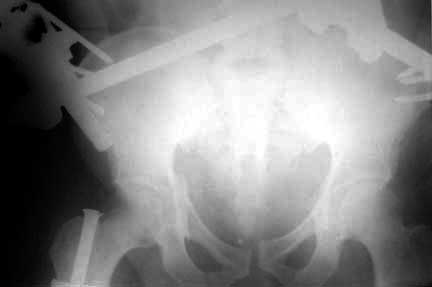

Middle aged male who was injured when a log of wood fell on him ina saw mill. Haemodynamically patient stable. No visceral injuries detected. The following musculoskeletal injuries detected: 1) Closed fracture femur. 2) Pubic symphysis disruption. 3) Right inf pubic rami fracture. 4) Right acetabular fracture. Head of femur located. 5) Right Sacroiliac joint anterior opening.

Here are the post op pictures.